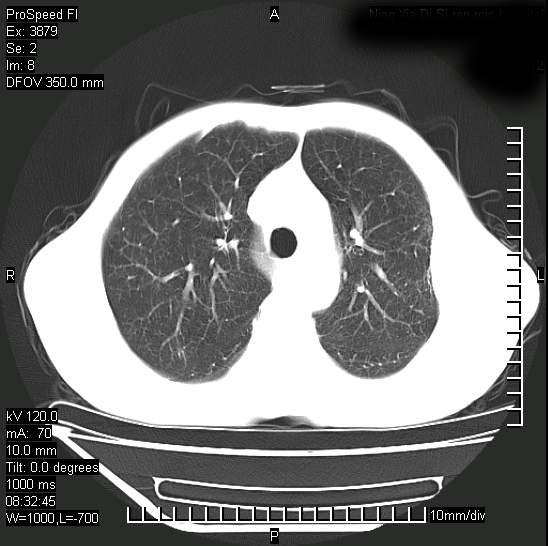

以下是引用37度在2008-6-6 11:20:00的发言:[br]1.包裹性积液,多考虑结核性;[br]2.穿刺术后改变。